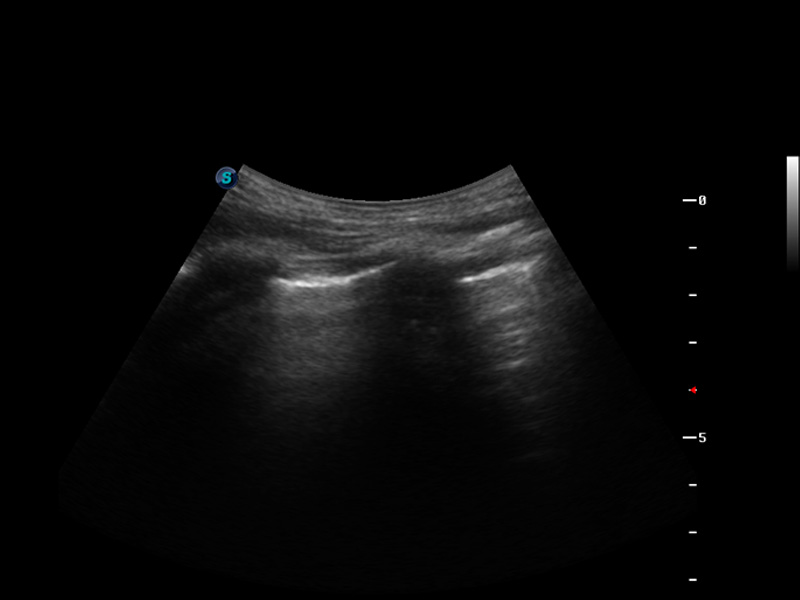

S9便携式彩色多普勒超声诊断仪是milan米兰研发的高端便携彩超设备,外观设计新颖、产品性能卓越。S9在便携超声领域采用了突破传统的触摸屏交互设计,并以先进的软件硬件技术和设计理念,为您带来清晰的图像质量、稳定的工作性能和便捷的操作体验。